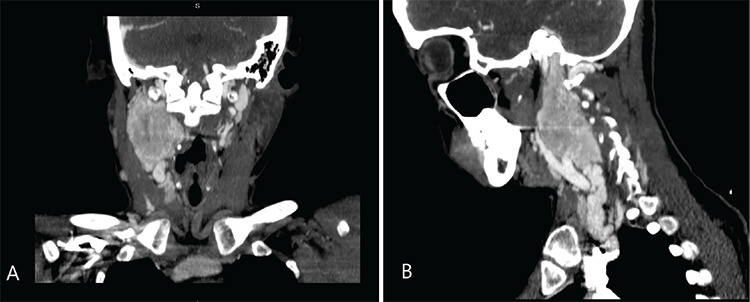

Objective: To investigate head and neck paraganglioma cases treated at a tertiary center from 2007 to 2023. The research includes a thorough examination of published studies that have focused on long-term outcomes. The additional goal is to contribute to the existing knowledge on head and neck paraganglioma, with a particular emphasis on refining diagnostic algorithms, treatment selection, and follow-up procedures.

Methods: A total of 44 patients were retrospectively analyzed, and 39 were included. Demographic information, symptoms, radiological examination results, types, stages, and postoperative complications were recorded. A review was conducted to select articles that reported single-center experiences with large cohorts, long follow-ups, and different treatment modalities since 2010.

Results: The mean age of the patients was 54 years, and the female/male ratio was 3.55:1. Among the 39 cases examined, 18 and 19 were identified as cervical paraganglioma and 19 as temporal bone paraganglioma. All patients initially underwent surgical resection. The mean follow-up duration was 5.42 years. Four residual cases and two recurrences were identified postoperatively, and a Gamma Knife was used as additional treatment. Subsequently, 17 articles were selected and summarized, and then a flowchart was prepared showing the possible options for diagnosis, treatment, and follow-up.

Conclusions: Preoperative staging is essential for surgical planning and predicting potential intraoperative complications. Based on our findings and review of the articles, we have prepared a flowchart that includes all possibilities depending on the tumor stage to help in the diagnosis, treatment, and follow-up of head and neck paragangliomas.